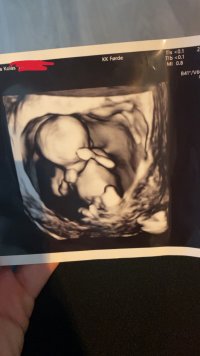

Det er veldig tidlig for å se kjønn, men det ser ut som en jente nå, men det kan endre seg. Det er veldig små marginer for å måle mer eller mindre så du er nok 12+1, noen vokser litt mer og andre vokser litt mindre også, ofte er gutter litt større enn jenter også. Jeg tror kanskje nuben vil reise seg litt på denne og at det er en gutt, men enn så lenge ser det ut som jenteNoen som kan se noe kjønn på disse bildene?

Klarte ikke vente lenger så booket UL i morgen(da er jeg 14+1). Blir spennende å se om legen klarer å se noe. Hun mente hun skulle klare det så lenge fosteret ligger greitDet er veldig tidlig for å se kjønn, men det ser ut som en jente nå, men det kan endre seg. Det er veldig små marginer for å måle mer eller mindre så du er nok 12+1, noen vokser litt mer og andre vokser litt mindre også, ofte er gutter litt større enn jenter også. Jeg tror kanskje nuben vil reise seg litt på denne og at det er en gutt, men enn så lenge ser det ut som jente![]()